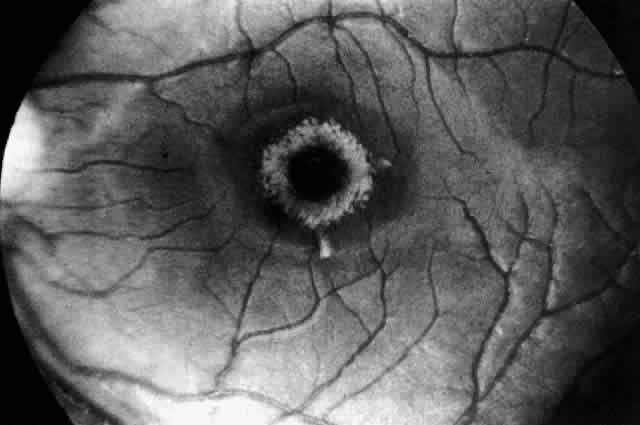

THE GM2-GANGLIOSIDOSES The GM2-gangliosidoses are a class of disorders resulting from the deficiency of ß-hexosaminidase A (Hex A) or ß-hexosaminidase B (Hex B) and Hex A. Hex A is an essential enzyme that normally cleaves the terminal sugar from the Tay-Sachs ganglioside and is identified by its action on artificial substrates. Expression of Hex A activity requires three separate gene products: an α-subunit, a ß-subunit, and an activator protein, all encoded by genes located on two different chromosomes. Various forms of GM2-gangliosidosis have been described (Tay-Sachs disease, Sandhoff's disease, and variants) that can be traced to mutations in one or another of these three loci. The effect is usually a deficiency of Hex A activity or a concomitant Hex B and Hex A deficiency, permitting a pathologic accumulation of GM2-ganglioside in neurons. Hex A is made up of two ß-subunits and two α-subunits, the latter coded for on the long arm of chromosome 15, The activator protein locus is located on chromosome 5. Hex B is a tetramer made up of four identical ß-subunits also coded for on chromosome 5 (Fig. 2). The extent of the deficiency of hexosaminidase determines the rate of ganglioside accumulation and hence the time of onset and the clinical severity of the disease. The most severe form is classic infantile Tay-Sachs disease characterized by an almost complete absence of Hex A activity with preservation of Hex B; hence it is called the B variant. Less severe forms have been described that are characterized by the presence of residual but insufficient levels of Hex A activity. These milder variants present as juvenile, chronic, or adult forms of GM2-gangliosidosis (see Table 1). Tay-Sachs Disease (Infantile GM2-Gangliosidosis Type I) Infantile GM2-gangliosidosis type I is the most common example of a sphingolipid storage disease. It is inherited as an autosomal recessive disorder because of a mutation in the α-locus on chromosome 15, resulting in a deficiency of Hex A. The carrier frequency for this gene is very high among those of Ashkenazi Jewish or French Canadian descent (1/27 and 1/25 individuals, respectively). Tay-Sachs screening programs primarily target these two populations. CLINICAL MANIFESTATIONS. Children with Tay-Sachs disease show neurologic signs at birth. Observant parents notice an increased startle reaction to sound and hypotonia at 2 to 3 months of age. The startle response is a reflex myoclonic jerk consisting of tonic extension, adduction and elevation of the arms, clenching of the hands, flexion or extension of the legs, a startled facial expression, and a sharp cry. A brief metallic bang elicits it more reliably than a hand clap, and although it has been called hyperacusis, the sign does not denote increased auditory sensitivity. Occasionally the response is produced by light flashes and tactile stimuli. The increased startle reflex is characteristic of the early stages of Tay-Sachs disease and is without overt electroencephalogram (EEG) correlate. At 12 to 18 months of age it is superseded by segmental and diffuse myoclonus and by prolonged tonic seizures, both spontaneous and stimulus driven. The spikes and sharp waves of the EEG in the second year are replaced by a flattened, featureless, slow EEG by the third year. The exaggerated startle response is not restricted to Tay-Sachs and Sandhoff's diseases. It occurs in other conditions, such as GM1-gangliosidosis, although not as early or as persistently. Apart from this sign and mild hypotonia the child appears to develop normally until the fourth to sixth month of life when signs of mental retardation and loss of motor skills become manifest. The infant fails to sit up or walk, marked axial hypotonia in combination with pyramidal signs develop, and there is variable spasticity of the limbs. After 18 months of age, progressive deafness, blindness, and megalencephaly occur as a result of storage of GM2-ganglioside and cerebral gliosis. By the end of the third year the child is demented, decerebrate, and blind. Progressive cachexia and aspiration pneumonia usually lead to death before age 10. OCULAR MANIFESTATIONS. Tay, a British ophthalmologist, was the first to recognize the macular cherry-red spot in 1881 .1 In 1896, Sachs, an American neurologist, emphasized the association of this ocular manifestation with signs of progressive involvement of the central nervous system (CNS) characterized by dementia, blindness, convulsions, and early death.2 Recognition of the cherry-red spot at the macula is a major diagnostic criterion of Tay-Sachs disease (Fig. 3). It is caused by the accumulation of intracytoplasmic membranous bodies in retinal ganglion cells.

The circular appearance of the fundoscopic lesion reflects the anatomy of the macula. No ganglion cells are present at the very center of the macular region, the foveola, and the central red spot simply represents the normal choroidal background color. The ganglion cell layer surrounding the foveola is several cells thick, and loading of these neurons by storage products results in loss of retinal transparency and a white parafoveal halo. Peripheral to the macular region the ganglion cell layer is only one cell thick, and lipid accumulation in these cells is, therefore, less conspicuous. Tay-Sachs disease is also the most common storage disease causing macular cherry-red spots (Table 2).3 The variation in the shade of the red spot reflects racial fundus pigmentation. The halo is opaque, slightly elevated, and 1.5 disc diameters in width. The outer border is less sharp than the inner border.